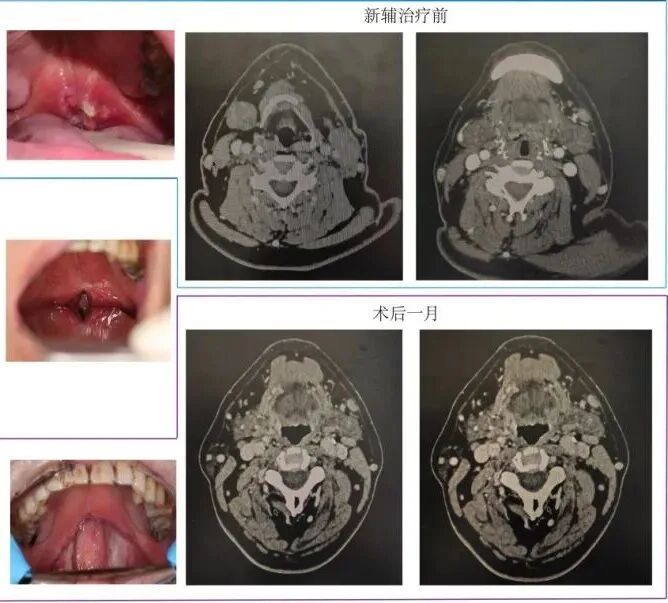

据了解,患者于今年7月因软腭鳞癌伴双颈淋巴结转移,到席庆教授诊室求诊。经过多学科联合会诊,认为患者直接手术具有较大复发风险,预后效果极差,建议行术前新辅助免疫治疗+TORS(Trans oral robotic surgery)+术后辅助同步放化疗的综合治疗方案。随后,患者接受了两个周期的新辅助免疫治疗,口咽部肿瘤及转移肿大淋巴结明显消退,为机器人手术提供了良好的条件。

手术过程中,先由刘林教授团队进行经乳晕切口清扫双侧淋巴结,之后由席庆教授团队实施经口机器人手术,通过特殊开口器准确充分暴露肿瘤位置,在肿瘤外扩大切除肿瘤。经病理检测手术切缘部分,显示全部为阴性,手术取得圆满成功!